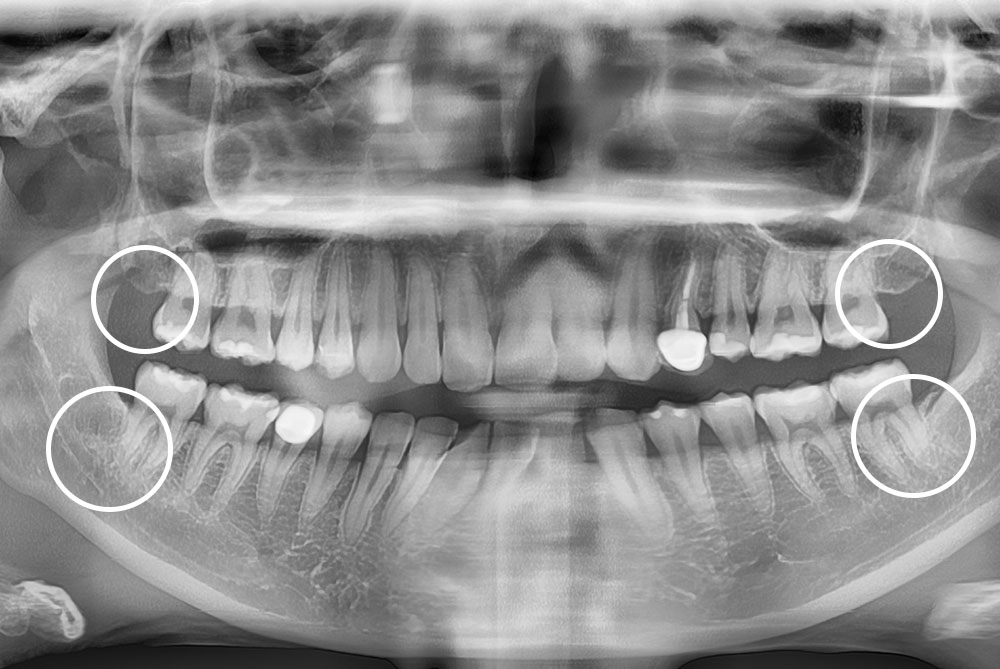

[사랑니] 매복 사랑니 발치

치료전 : 2017-06-28